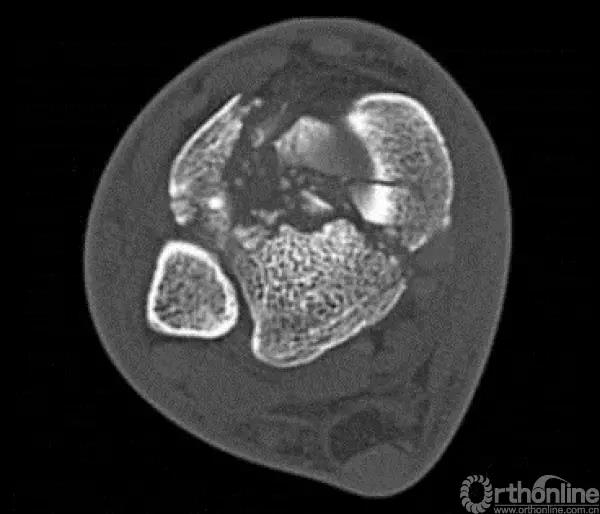

Pilon骨折手术入路选择原则一般取决于最适合进行关节面复位的入路。cole在2013年jot发表的文章描述了pilon骨折的骨折线图根据多例病例汇总到一起,颜色越深则越骨折线经过的可能性越大。

他将pilon骨折大致的骨块进行了分类,分别为后、前内、前外三个骨折块。Pilon骨折的入路一共有5个,前内、前正中、前外、后内、后外。

2.中心粉碎骨折

对于中心粉碎骨折需要充分牵引、撑开,将关节面的骨折块先找到摆放在合适的位置,用克氏针将关节面的骨块应用排筏技术先固定好,从下方观察关节面的复位情况,并且确认骨块不会向上推起,适当植骨,然后将骨块前后和左右进行压实后进行固定。